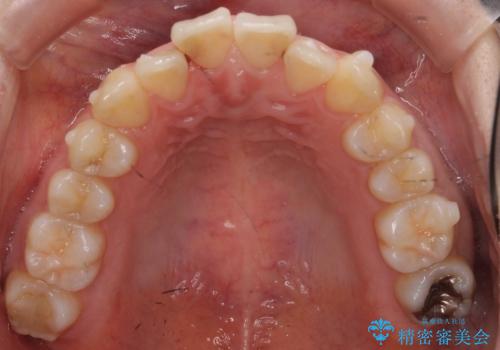

軽度の前歯のがたつき 下の前歯が生まれつき少ない

- 前歯のがたつきを主訴に来院。

下の前歯が生まれつき3本でした。

そのため、上の前歯が少し余るような形で出っ歯になっていたため、スペースを作って引っ込めています。

下を3本でそのまま並べてあるため、上下の正中は合いません。

合わせようとすると抜歯か、下の隙間を無理やり開けてブリッジとなりますが、そこまでするメリットがないため、下はそのままの歯の数を生かしています。